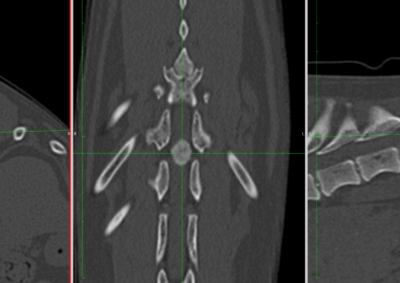

脳神経外科 注意 ボタンをクリックした先に、治療中および手術中の画像が説明で使用されている場合がございます。 そのような画像に弱い方は閲覧なさらないようお願いいたします。 脳神経外科 セメントレス環軸固定術 脳神経外科 Hemi-Laminectomy 脳神経外科 Ventral Slot 脳神経外科 椎体固定術 脳神経外科 Hemi-Laminectomy 脳神経外科 脊髄亜膜下憩室切除 脳神経外科 椎間板ヘルニア G1 脳神経外科 椎間板ヘルニア G2 脳神経外科 IVDD G5 脳神経外科 Ventral Slot 脳神経外科 Ventral Slot 脳神経外科 Ventral Slot 123456> 症例カテゴリー 放射線治療整形外科軟部組織外科脳神経外科内科腫瘍外科救急・集中治療リハビリテーション科腫瘍内科内視鏡科脳神経科呼吸器外科中医・漢方猫の腎移植循環器科電気化学療法